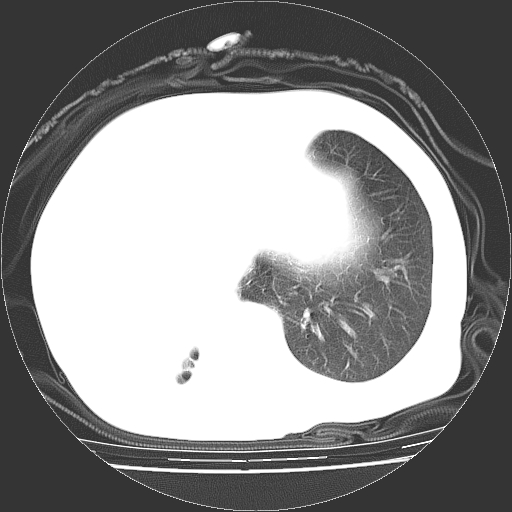

标题: CT23991:女,72岁,咳嗽、憋气一周。 [打印本页]

女,72岁,咳嗽、憋气一周,十年前曾患肺结核及胸膜结核。

右侧毁损肺,右侧纵隔疝

右侧毁损肺,右侧纵隔疝,左肺代偿!

1.右侧损毁肺伴胸膜钙化,2.左肺小结节灶,良性可能大,注意复查。3.肝脏左叶囊肿。4.先天性一侧肺不发育待出外(右侧胸廓无明显塌陷)。对比原片应该非常有帮助。